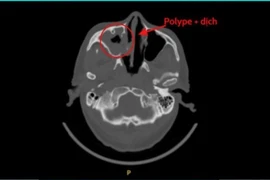

Viêm xoang nấm tiến triển âm thầm, triệu chứng không điển hình nên dễ bị bỏ qua. Ổ nấm phát triển thành từng mảng lớn trong hốc xoang, bào mòn xương...